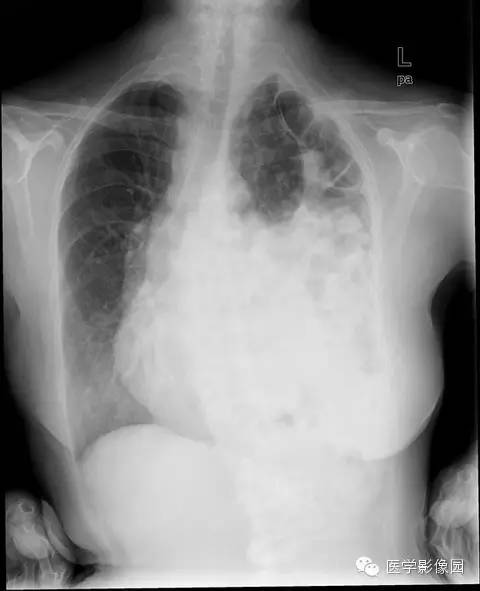

膈疝1例X线及CT影像表现

膈疝的形成除先天性膈肌融合部缺损和薄弱点外,还与下列因素有关:

①胸腹腔内的压力差异和腹内脏器的活动度;各种引起腹内压力增高的因素如弯腰、排便困难和怀孕等均可促使腹内脏器经膈肌缺损和薄弱部进入胸内。

②随着年龄增长,膈肌肌张力减退和食管韧带松弛,使食管裂孔扩大,贲站或胃体可以经过扩大的食管裂孔突入后纵隔。

③胸部外伤尤其胸腹联合伤引起膈肌破裂。